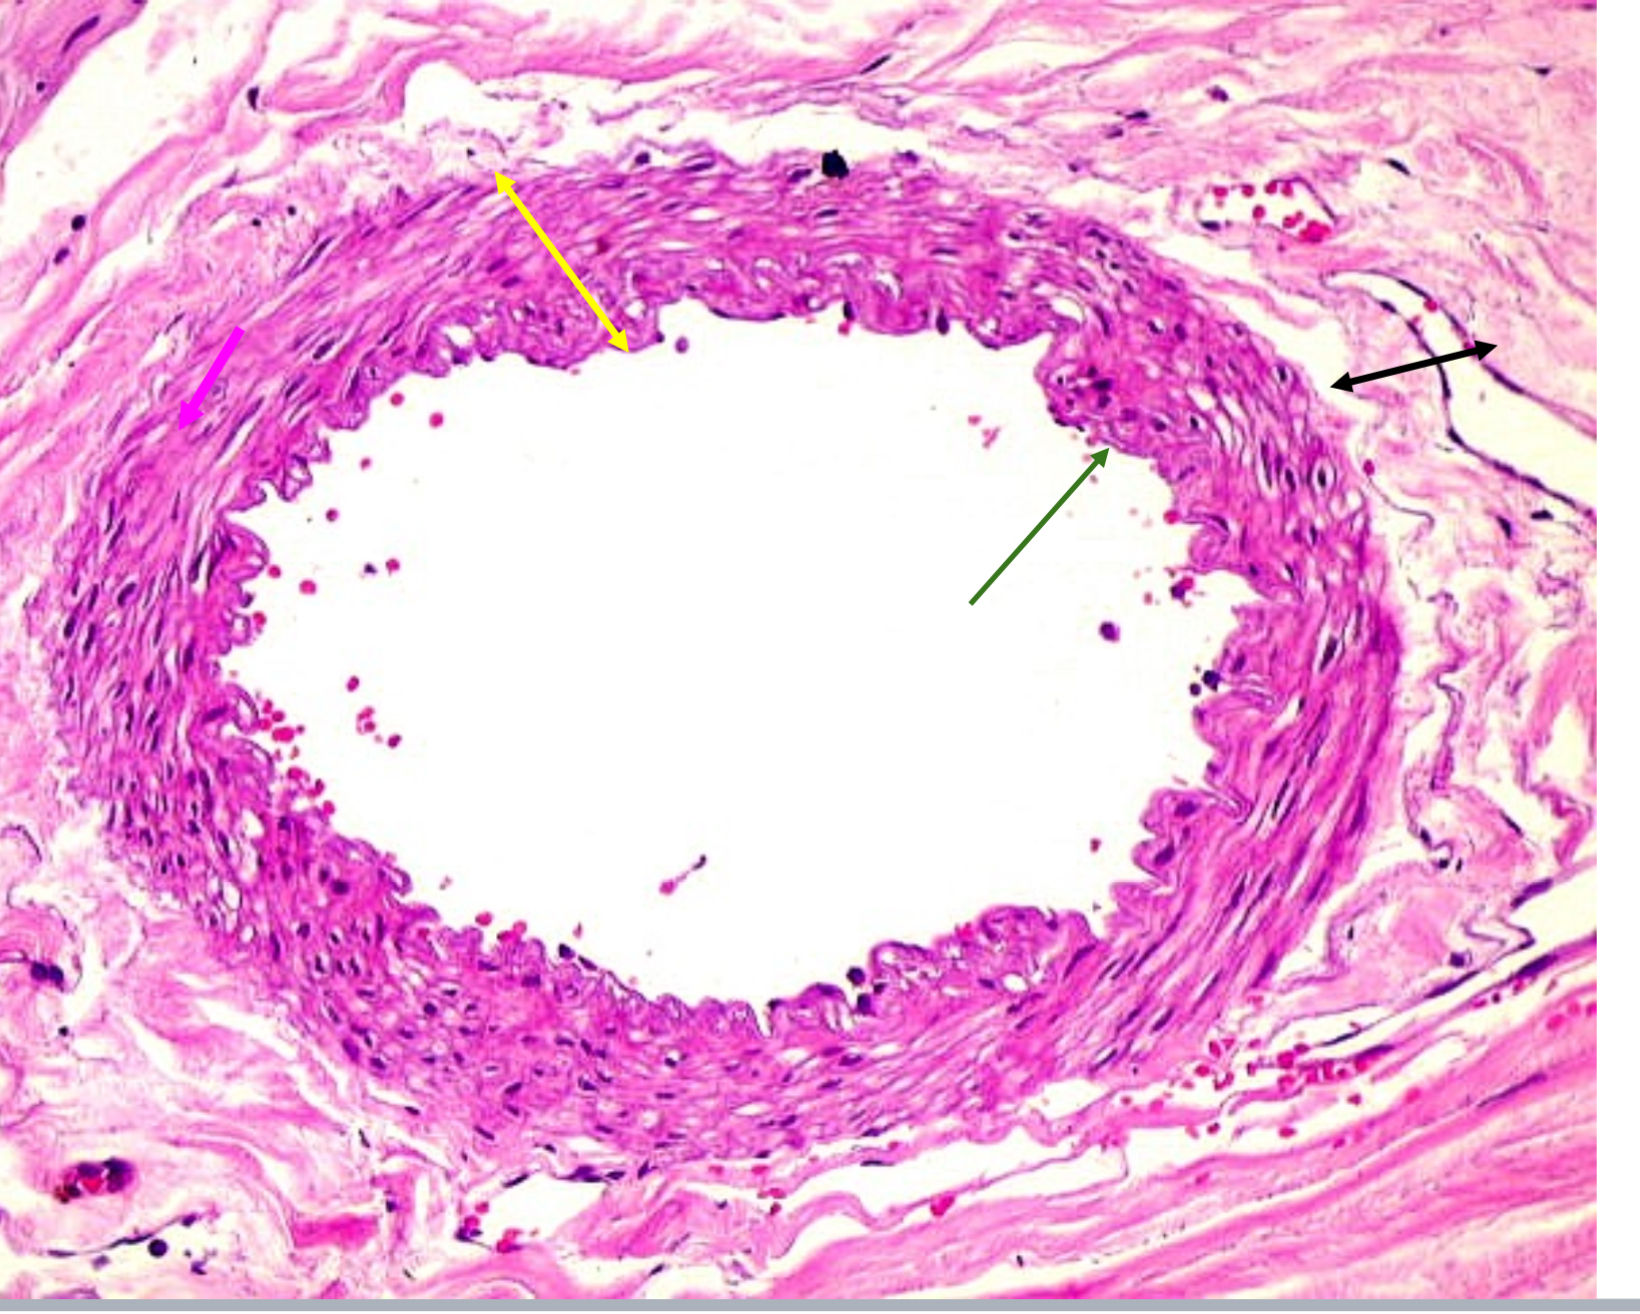

Tunica intima

Name the blue arrow

Lines lumen and release vasoactive chemicals

Function of tunica intima

Venous valves

Name the pink arrow

Prevent backflow of blood

Function of venous valves

Tunica media

Name green arrow

Vasoconstriction and vasodilation

Function of tunica media

Tunica externa

Name the purple arrow

Anchor and bind vessel

Function of tunica externa

Artery

Artery or vein?

Tunica intima

Name the green arrow

Tunica media

Name the yellow

Tunica externa

Name the black